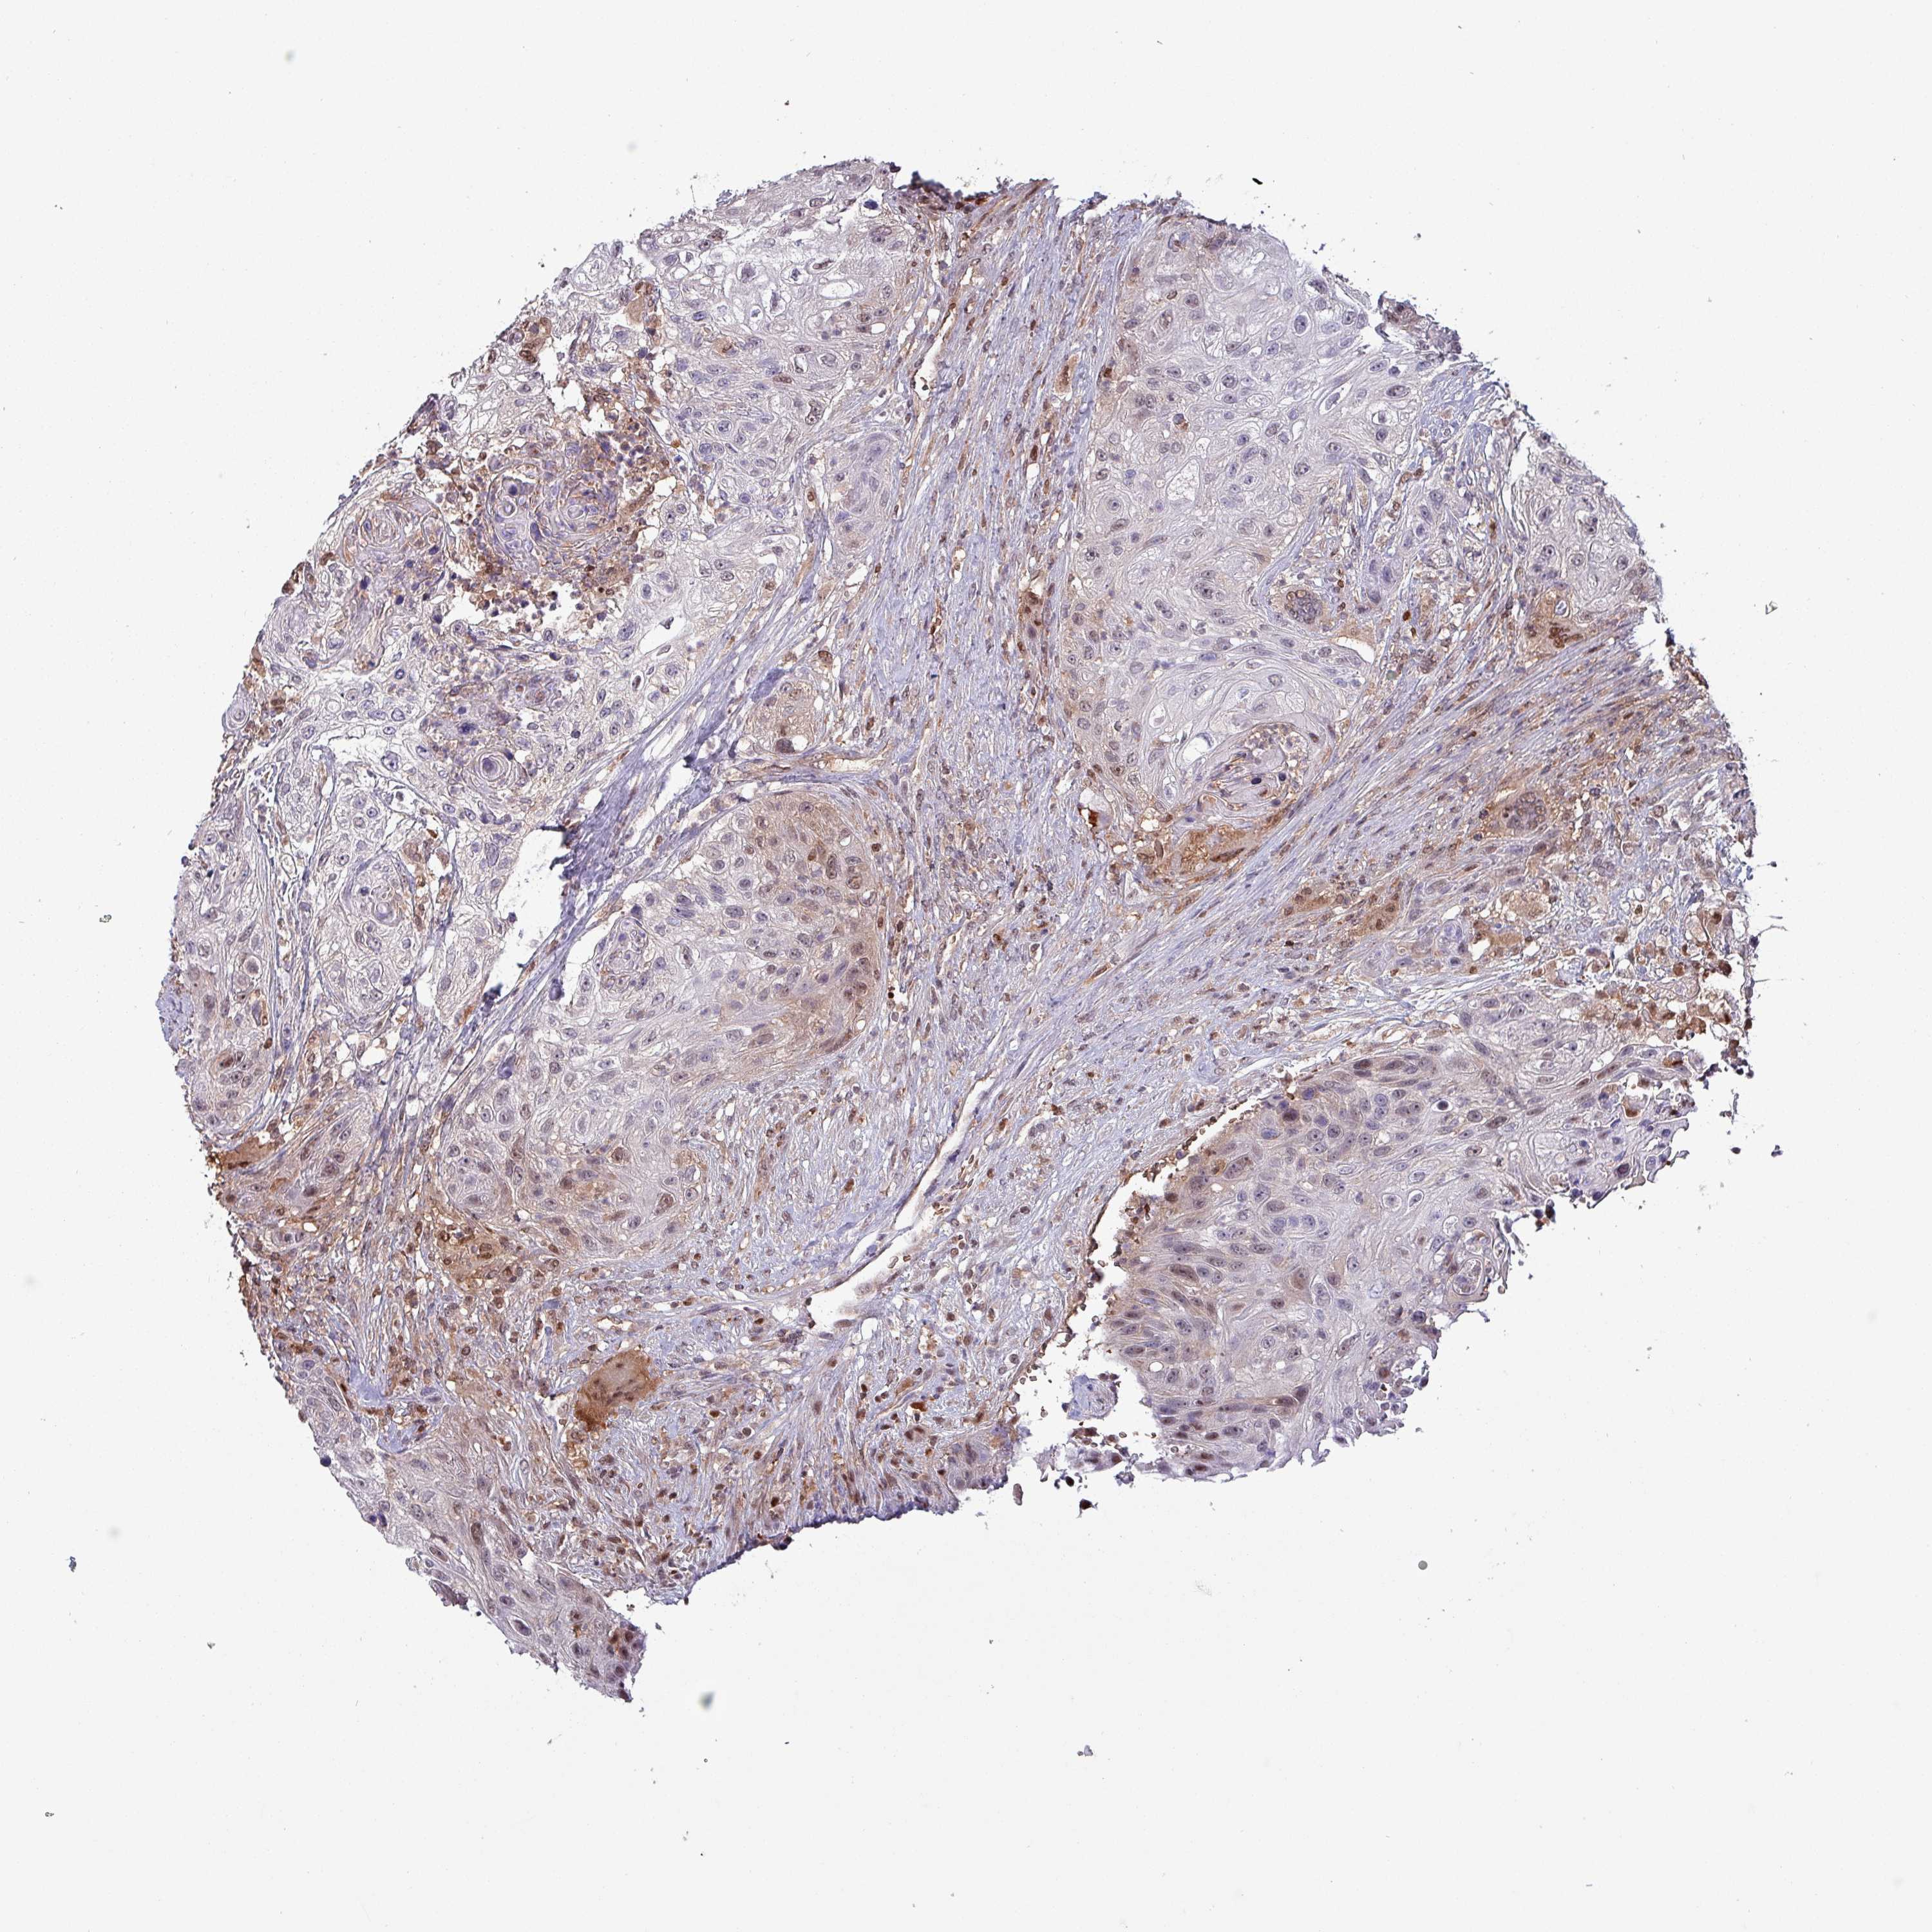

UROTHELIAL CANCER - Protein expressioni

A mouse-over function shows sample information and annotation data. Click on an image to view it in a full screen mode. Samples can be filtered based on level of antibody staining by selecting one or several of the following categories: high, medium, low and not detected. The assay and annotation is described here.

Antibody stainingi

Antibody staining in the annotated cell types in the current human tissue is reported as not detected, low, medium, or high, based on conventional immunohistochemistry profiling in selected tissues. This score is based on the combination of the staining intensity and fraction of stained cells.

Each image is clickable and will lead to virtual microscopy that enables deeper exploration of all samples and also displays staining intensity scores, fraction scores and subcellular localization as well as patient and tissue information for each sample.

Antibody HPA046995

Antibody HPA050327

Urothelial carcinoma, High grade

Urothelial carcinoma, Low grade

Urothelial carcinoma, NOS